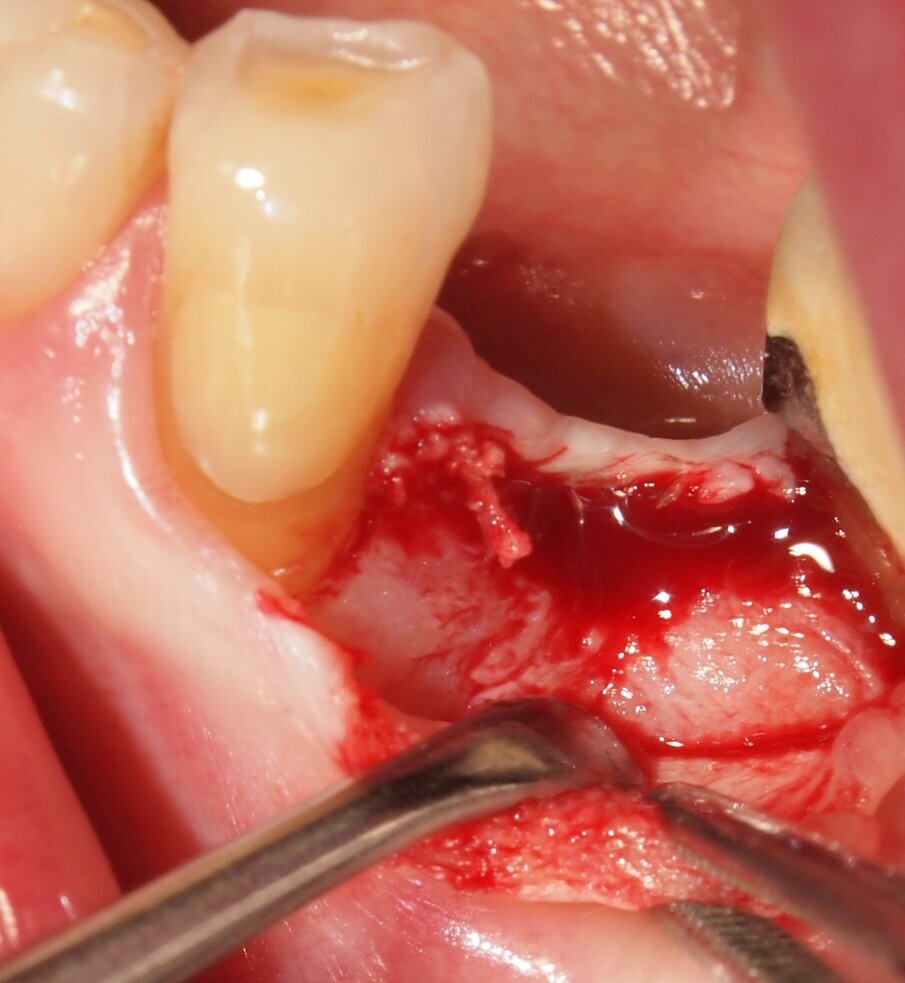

Fig. 6 - Caso clinico 1. Sollevamento di un lembo mucoperiosteo ed esposizione della corticale ossea. Si apprezza macroscopicamente l’assenza di fenomeni di carbonizzazione e danni termici dei tessuti molli e del tessuto osseo che mantiene un’adeguata vascolarizzazione.

Fig. 7 - Caso clinico 1. Posizionamento di una fixture di dimensioni adeguate al caso clinico in esame.